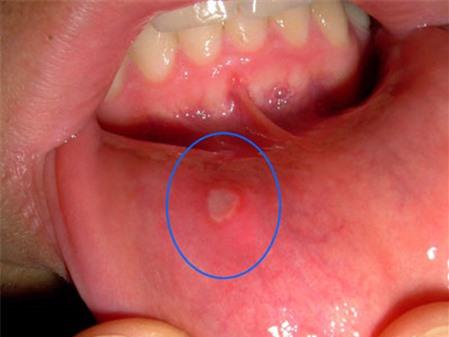

bị suy giảm. Từ đó vi khuẩn dễ dàng tấn công vào khoang miệng, gây ra những vết lở loét

ở lưỡi, nướu và các vị trí khác trong miệng. Ngoài ra do cơ thể bị thiếu hụt nước dẫn đến cơ nhiệt tăng cao, nóng trong người. Tuỳ theo cơ địa

của mỗi người mà các vết lở loét xuất hiện nhiều hay ít, nhanh hay chậm, to hay nhỏ. Thực tế có nhiều người thường ăn đồ xào, chiên, ăn bánh mì, ăn mì gói hàng ngày, ít uống nước mà không bị nhiệt miệng là do cơ địa “mát”, khả năng miễn dịch cao. Ngược lại, có người kiêng khem đủ thứ vẫn bị bệnh này.

Nhiệt miệng là bệnh lành tính nhưng nó khiến bệnh nhân đau rát, khó chịu, ăn uống không ngon, giảm khả năng làm việc, học tập. Nguyên tắc cần và đủ để phòng và điều trị nhiệt miệng là làm mát cơ thể mọi lúc mọi nơi.